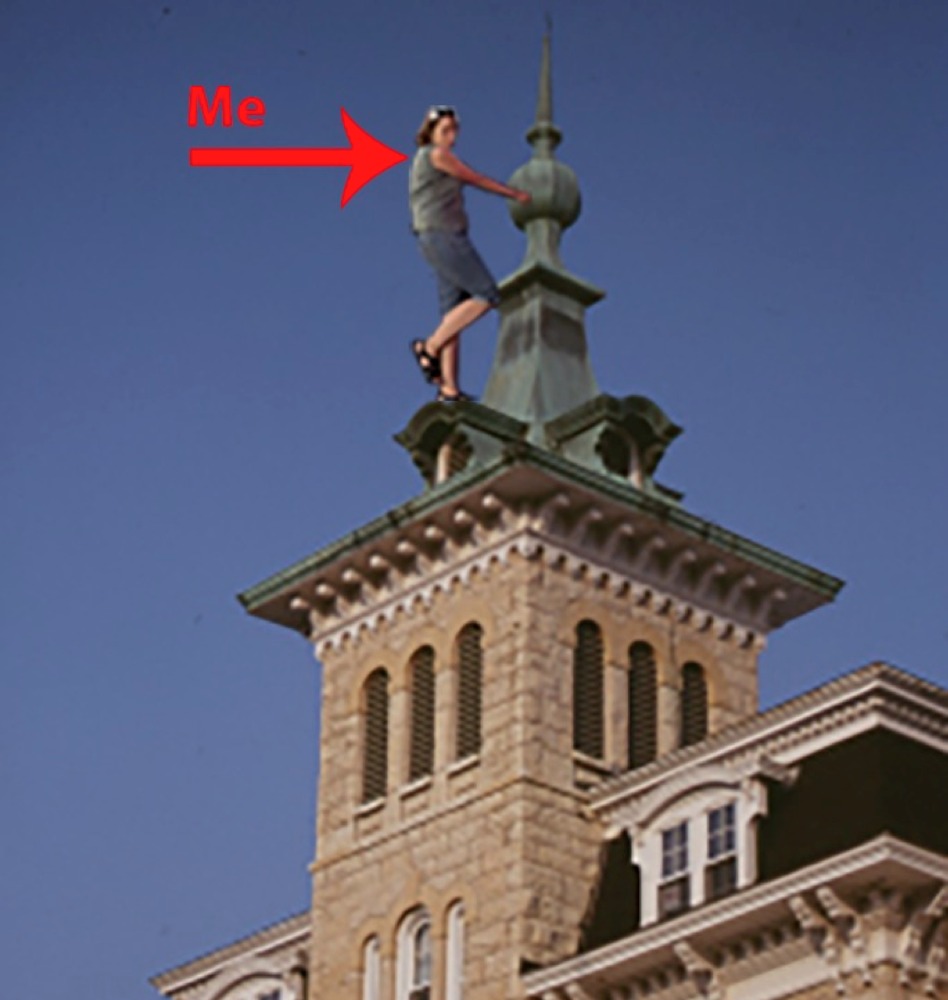

I have severe scoliosis with an S-curve & a twist at one end & a hump at the other (I was the Hunchback of North Central College).